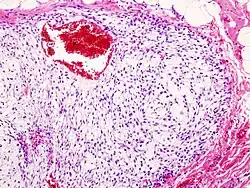

Ein Chondrosarkom ist ein maligner Knochentumor, dessen Zellen Knorpelmatrix, jedoch im Gegensatz zum Osteosarkom keine Knochensubstanz (Osteoid) bilden. Anders als das Chondrom weist das Chondrosarkom ein größeres Zellreichtum, Pleomorphie und Kernatypien auf.[1]